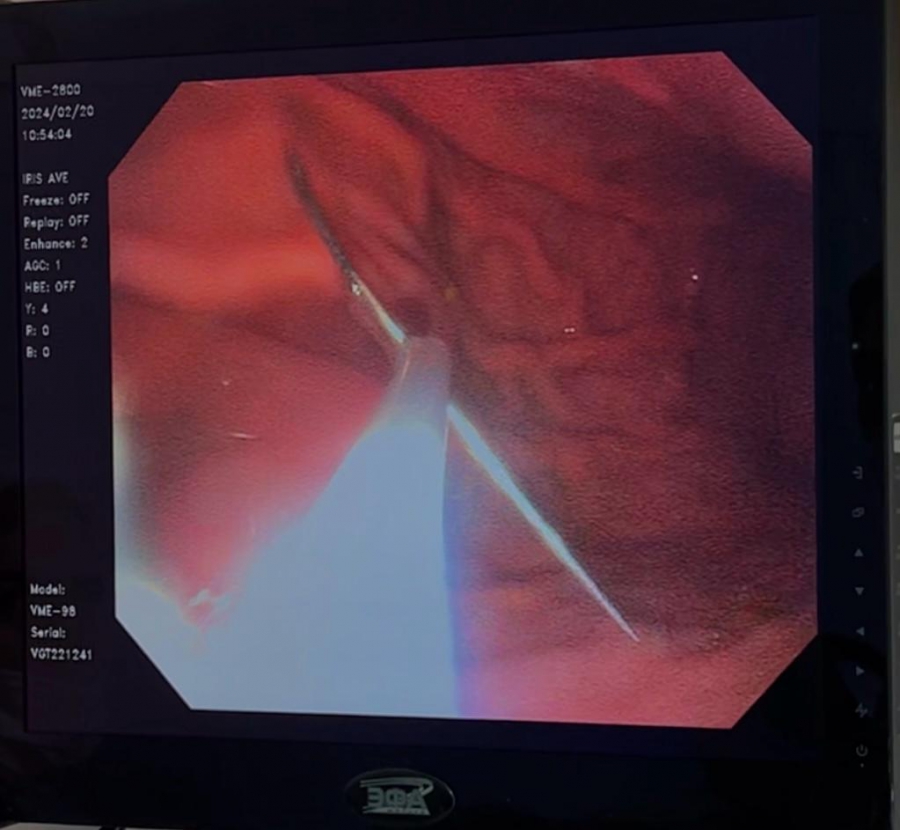

Сама пациентка рассказала, что боли появились четыре дня назад после приема пищи, по поводу чего обращалась в частные клиники к неврологу и гастроэнтерологу. Из-за отсутствия эффекта от лечения женщине выполнили эзофагогастродуоденоскопию (ЭГДС), во время которой в верхней трети тела желудка обнаружили швейную иглу.

Пациентку госпитализировали в горбольницу, где ей провел эндоскопическое удаление инородного тела из желудка. Иглу в 3,2 см удалось без последствий извлечь из желудка.